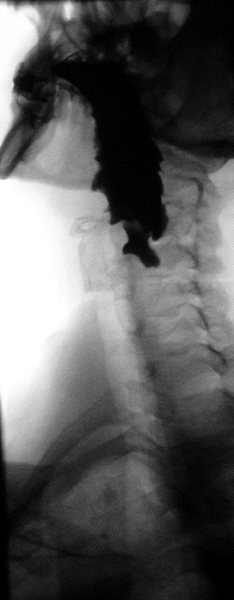

A Zenker's diverticulum, also pharyngeal pouch, is a diverticulum of the mucosa of the human pharynx, just above the cricopharyngeal muscle (i.e. above the upper sphincter of the esophagus). It is a pseudo diverticulum or false diverticulum (only involving the mucosa and submucosa of the esophageal wall, not the adventitia), also known as a pulsion diverticulum.

When there is excessive pressure within the lower pharynx, the weakest portion of the pharyngeal wall balloons out, forming a diverticulum which may reach several centimetres in diameter.

While traction and pulsion mechanisms have long been deemed the main factors promoting development of a Zenker's diverticulum, current consensus considers occlusive mechanisms to be most important: uncoordinated swallowing, impaired relaxation and spasm of the cricopharyngeus muscle lead to an increase in pressure within the distal pharynx, so that its wall herniates through the point of least resistance (known as Killian's triangle, located superior to the cricopharyngeus muscle and inferior to the thyropharyngeus muscle. Thyropharyngeus and cricopharyngeus are the superior and inferior parts of inferior constrictor muscle of pharynx respectively). The result is an outpouching of the posterior pharyngeal wall, just above the esophagus.[3]

A combination of the simple barium swallow and a thorough endoscopy will normally confirm the diverticulum.[4]